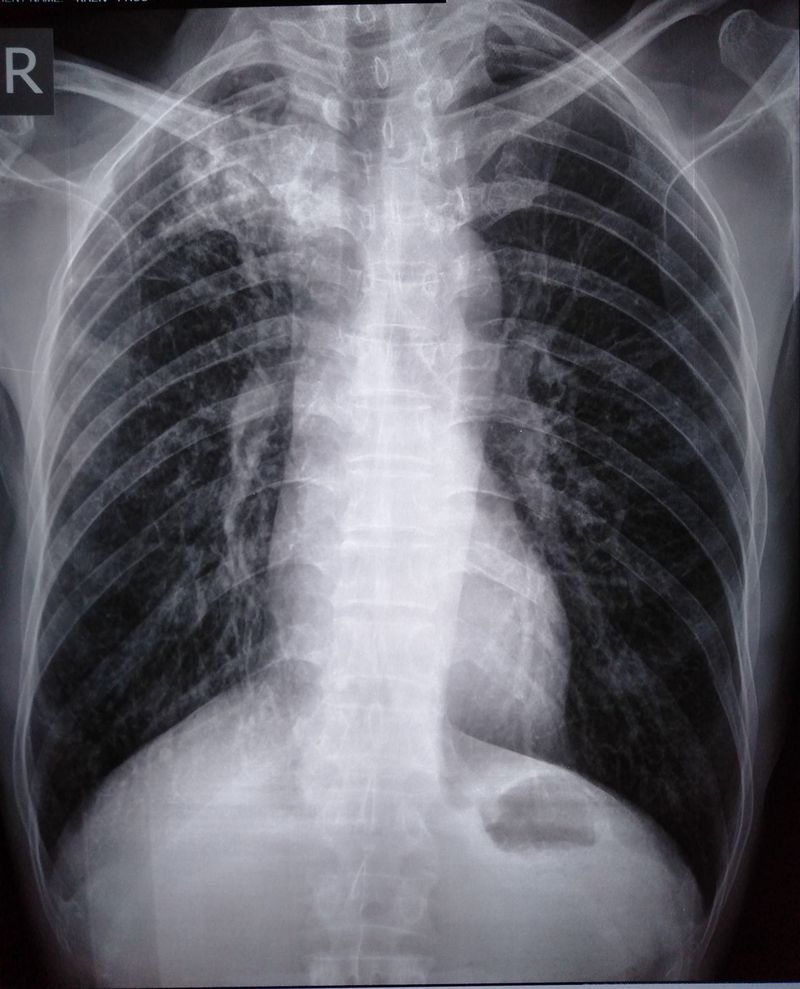

Patient 34yr come to emergency cc of hemoptysis

Infections

Pneumology